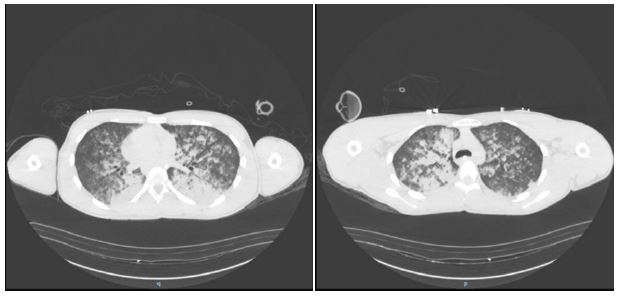

Upon emergence and extubation, the patient reported a sensation of “a lump in the throat,” followed by persistent coughing, hemoptysis, and oxygen desaturation (SpO2 82% on room air). Physical examination revealed tachypnea, use of accessory muscles, and diffuse wheezing. Initial chest radiography showed bilateral alveolar infiltrates. A contrast-enhanced chest CT scan (Figure 2) confirmed diffuse pulmonary edema without pleural effusion or cardiomegaly.

Images are Not Display Check it

Figure 2: Chest CT with IV contrast immediate postoperation (day 1 of hospitalization) revealed extensive patchy airspace opacities throughout the lungs bilaterally, more prominent centrally with a slight basilar predominance.